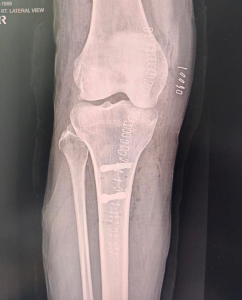

Lateral View (Side View)

Postoperative X-rays showing screw fixation and successful bone realignment after kneecap stabilisation surgery